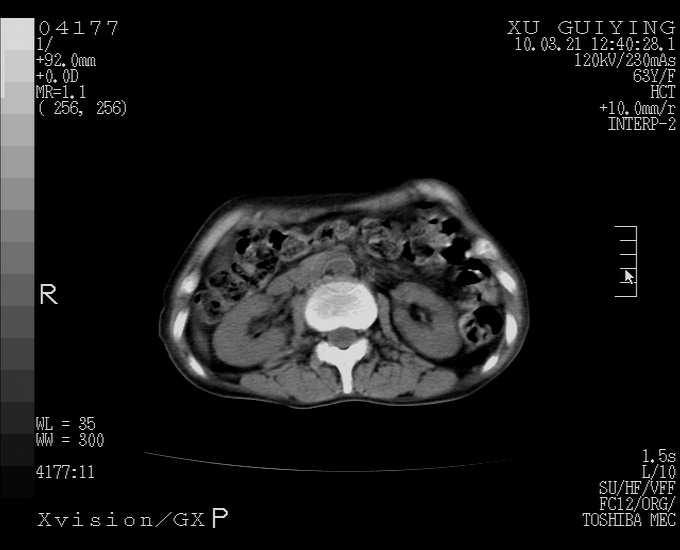

怎么没有增强呢?胆囊那么大,密度有些高啊。

胆囊体积增大,密度不均匀,结石不除外;胃壁增厚,考虑胃癌,建议增强。

胆囊体积增大,密度增高,较均匀,外缘也较光滑,应考虑胆囊炎。因为胃未充盈,不好说壁增厚。肝左叶及脾门处见低密度灶,有可能是血管瘤,不排除囊肿。建议超声检查或强化。

这就是江湖人称的“内科黄疸”, 肝内胆汁淤积症(ic)?